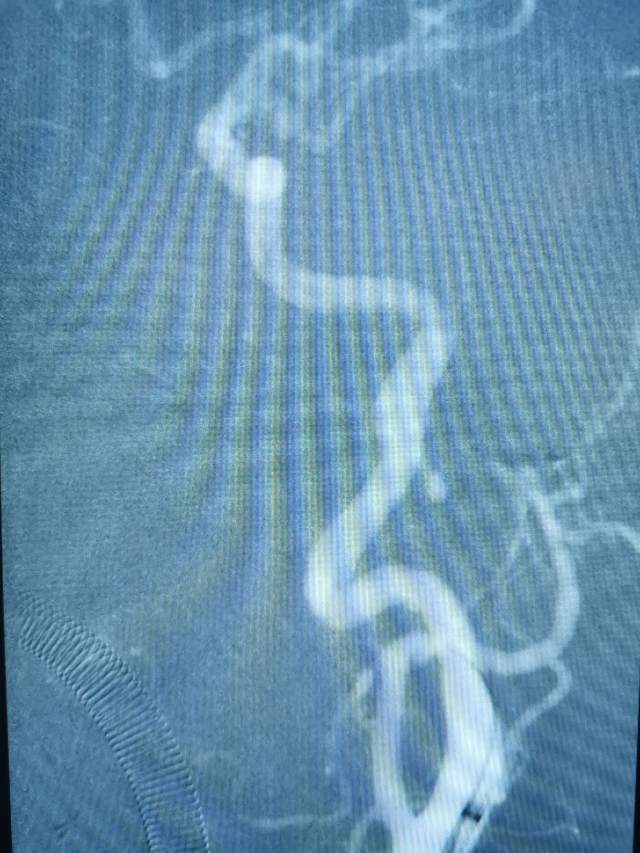

午夜,54岁中年女性,颅内多发动脉瘤破裂出血 ,一个左侧A1动脉瘤,一个左侧胚胎型大脑后动脉瘤(责任动脉瘤;起始部和远端上壁各见一个小泡,后面这个为破裂点;起始部累及粗大胚胎型大脑后动脉),

急诊绿色通道给予责任动脉瘤栓塞,远端破裂小泡完全不显影,近端瘤颈处小泡也基本不显影,胚胎性大脑后动脉保留良好。